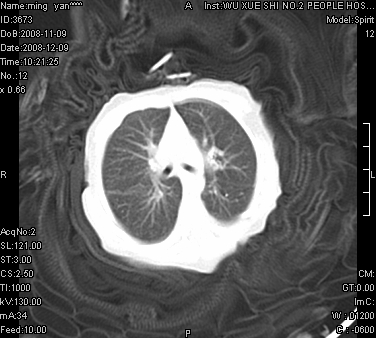

女.30天.咳嗽.喘3天.系三胞胎

考虑右肺下叶先天性肺囊肿,不除外合并右中叶肺发育不全

伴双肺感染

考虑右肺下叶先天性多发性肺囊肿可能。

考虑右肺下叶肺囊肿伴感染,右中叶节段实变或发育不全

这是一个先天性囊性腺瘤样畸形(congenital cystic adenomatid malformation,ccam),属于先天性肺发育异常,最近国外文献重新命名为先天性肺气道畸形(congenital pulmonary airway malformation,cpam),根据发生部位和畸形组织与气管、支气管的关系分成五型。本病以1岁以下婴儿多见,男性多于女性。病因为终末呼吸单元的异常增殖,形成多囊状结构。国内根据影响和病理表现分三型:ⅰ型为单个或多个大囊肿,直径大于2cm;ⅱ型为多个小囊肿,直径小于2cm;ⅲ型为大的非囊肿性病变,但显微镜下观察可见肿块由多发小囊组成(直径小于2mm)。本病可发生于肺内任何一部分,单侧肺占95%,中叶病变相对较少。